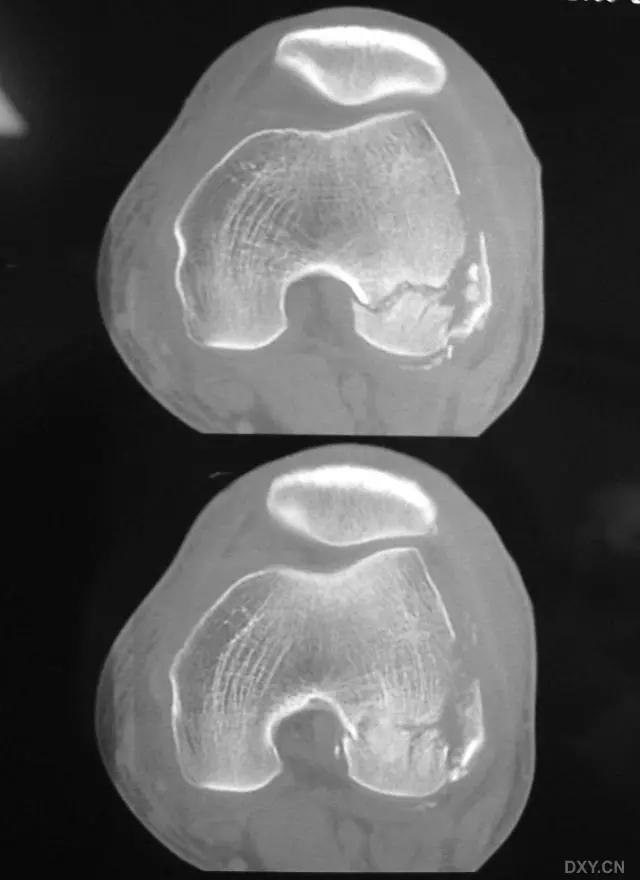

5. Hoffa 骨折

指股骨远端冠状面的骨折。

病例 1:一般股骨髁间、髁上粉碎骨折中含 Hoffa 骨折的不少见,但单纯后髁骨折则很少见。

正位片

侧位片

水平位 CT

第 2 例

第 3 例